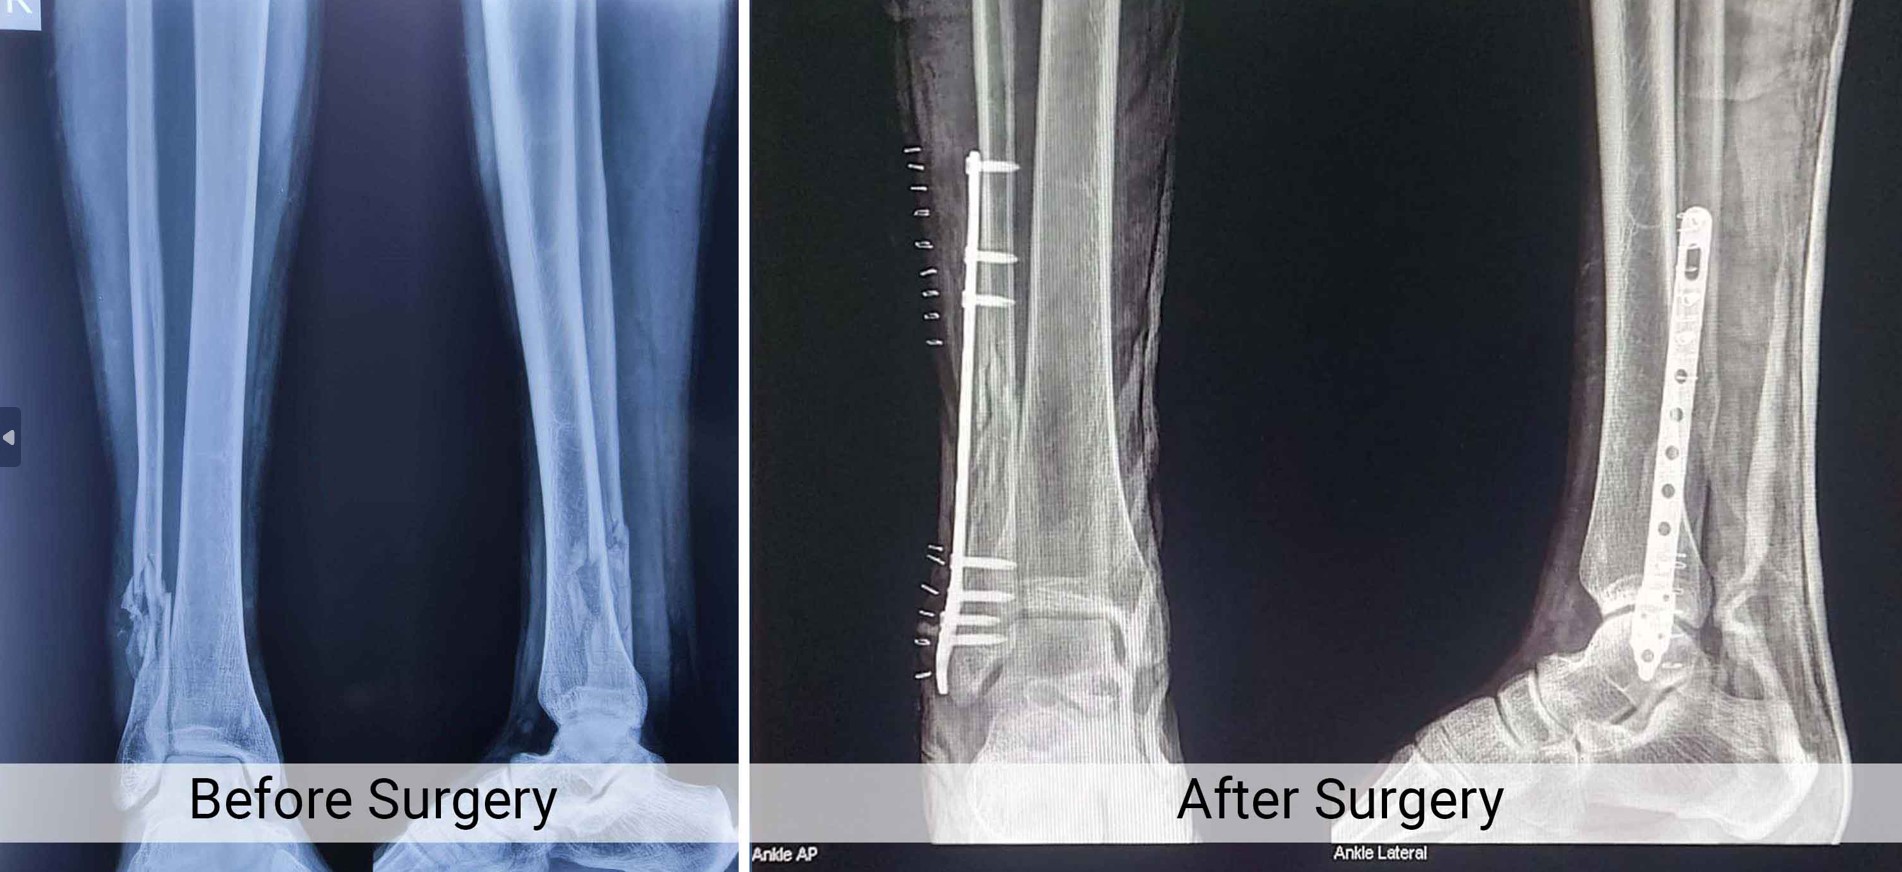

Trauma Fracture